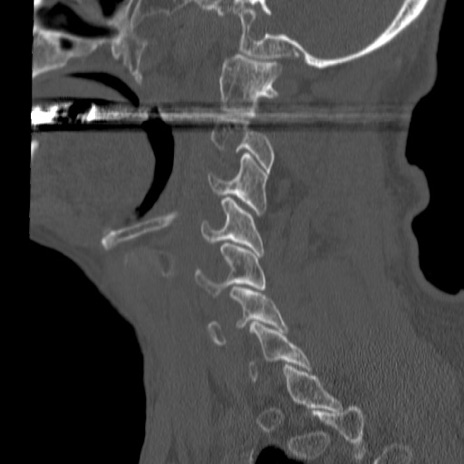

症例46 頚椎CT(矢状断像)

【症例】80歳代男性

【主訴】両側頚部〜上肢のしびれ

【現病歴】昨日、自宅内で転倒、その後より上記症状あり。意識障害なし。

【身体所見】両側上肢のallodynia(熱痛覚過敏)あり。MMTおよびDTRは正確な所見取れず。両上肢の挙上はなんとか可能。

異常所見と診断は?